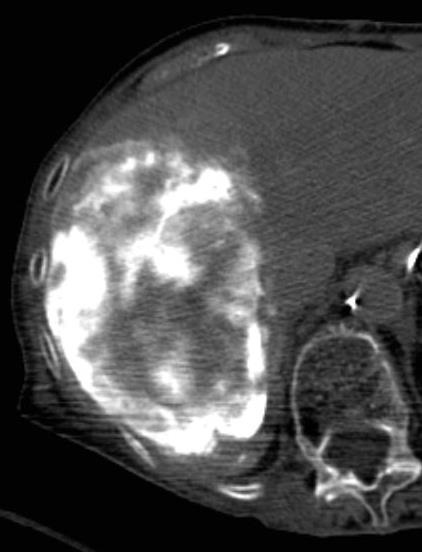

![]() ![]() ![]() ![]() 此图片的顺序待整理(查原文) ![]() ![]() ![]() ![]() Histologically-Proven Efficacy of Bland Embolization in a Patient with Net Liver Metastasis TAE 适应症之三:GIST

![]() ![]()

Hepatic artery embolization for liver metastasis of gastrointestinal stromal tumor following imatinib and sunitinib therapy.

Bland embolisation: GIST